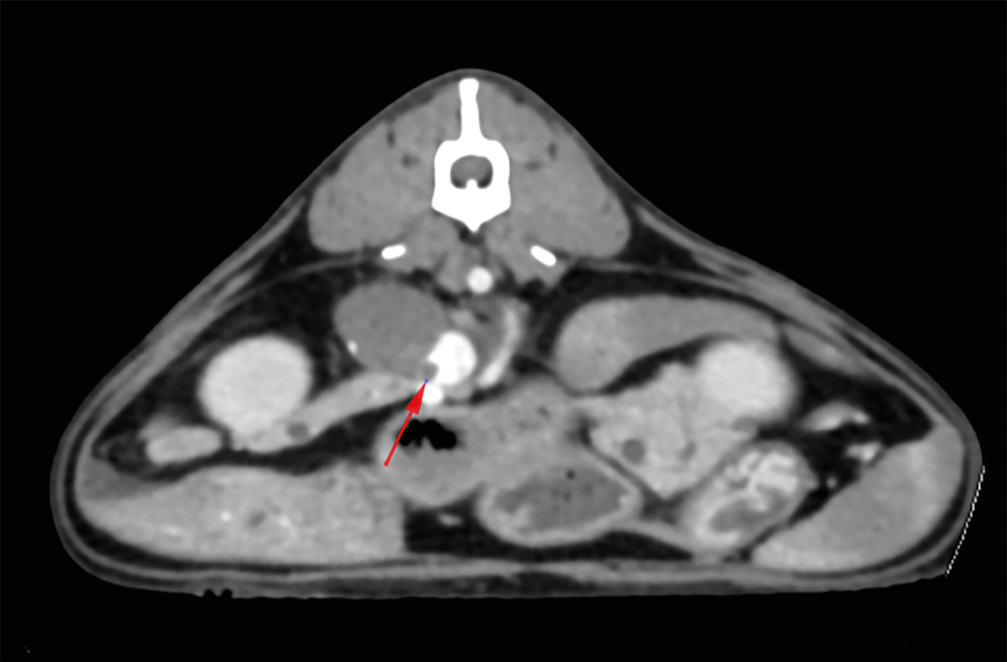

Tomografía computarizada

La prueba de elección previa a un tratamiento quirúrgico será la tomografía computarizada, ya que es una técnica superior para determinar la invasividad del tumor, identificar metástasis a distancia y planificar la cirugía (imagen 4).

En aquellos casos en los que no se realicen pruebas de imagen avanzada de tórax y abdomen, se recomienda complementar la ecografía abdominal con radiografías torácicas de tres vistas para descartar metástasis pulmonares.

Aunque la invasión vascular dificulta la cirugía, se ha descrito la extirpación exitosa de tumores adrenocorticales con invasión vascular (habitualmente en la vena cava caudal) (imagen 6).